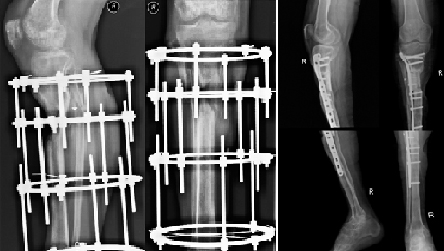

Пациент 37 лет обратился за помощью по поводе дефекта правой большеберцовой кости и укорочения правой голени до 17 см (см. фото слева). Дефект большеберцовой кости образовался в результате ранения. Пациенту, в связи с невозможностью восстановить длину конечности было предложено выполнить ампутацию на уровне бедра. Нами было проведено реконструктивно-восстановительное лечение, в котором были использованы клеточные технологии и метод Илизарова. В результате проводимого лечения дефект большеберцовой кости был замещен и восстановлена длинна конечности (см. фото справа).

Через 1,5 года пациент смог пользоваться своей правой ногой.